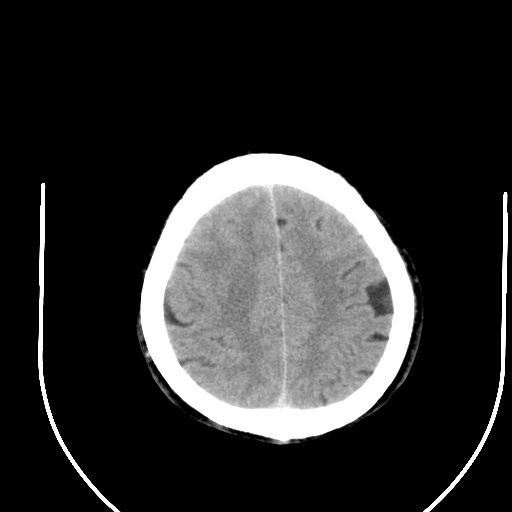

右侧基底节区脑出血并破溃入脑室。

1右侧基底节脑出血伴脑干出血并破入脑室系统脑疝形成2梗阻性脑积水

1)右侧基底节脑出血伴脑干出血并破入脑室系统。2)大脑镰下疝。3)梗阻性脑积水。

1、右侧基底节脑出血伴脑干出血并破入脑室系统。

2、大脑镰下疝。

3、梗阻性脑积水。